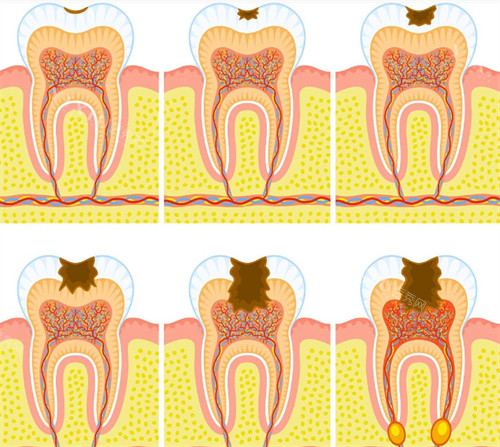

根管治疗:380 元起

后牙根管治疗:580 元起

补牙套餐:268 元起

3MP60 补牙:680 元起